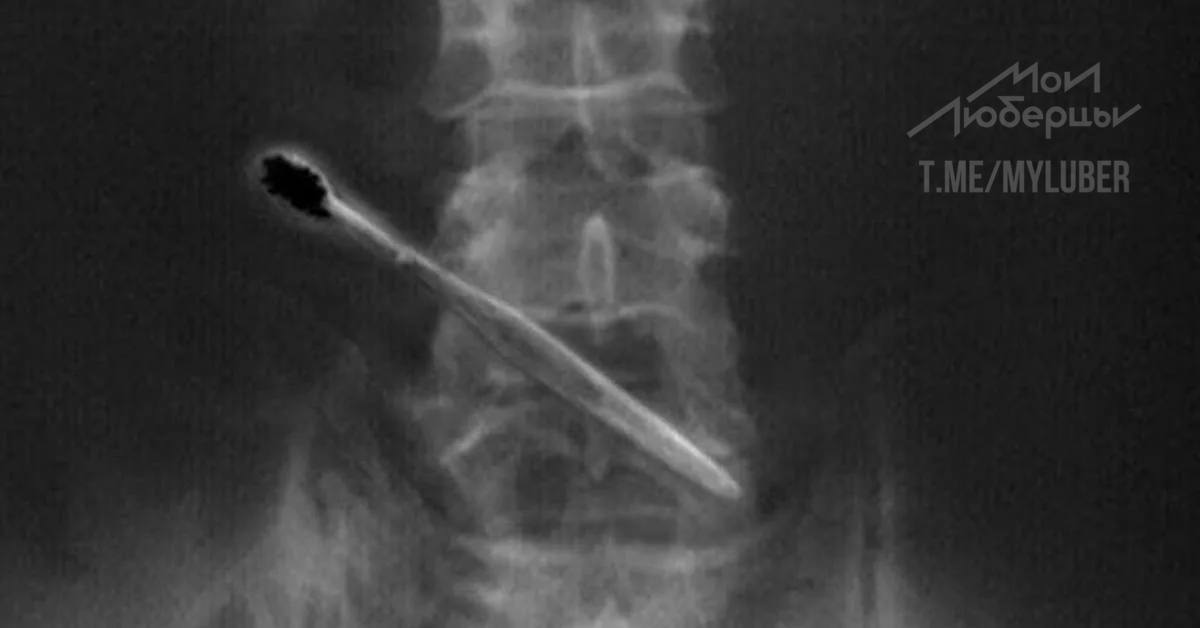

Удаление инородных тел из кишечника

Удаление инородных тел из кишечника 115 фотографий